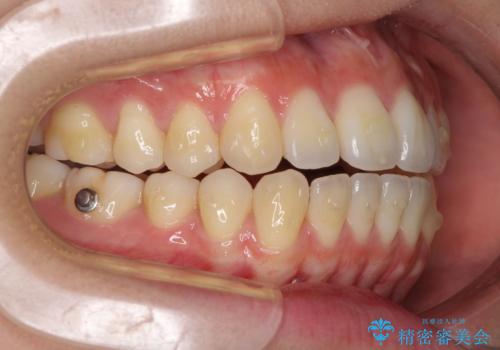

オープンバイトでかみにくい インビザラインによる矯正治療

- インビザライン

- 前歯の上下スペースによる食べにくさを気にして来院された患者様です。

インビザラインにより上下の前歯の隙間を閉じていくこととしました。

上下の奥歯を圧下させるようにすることで、前歯を接触させるように計画しました。

上下の隙間に舌が入り込むことがオープンバイトの原因であったため、舌の筋肉のトレーニングも並行して行い、後戻りの抑制を図りました。